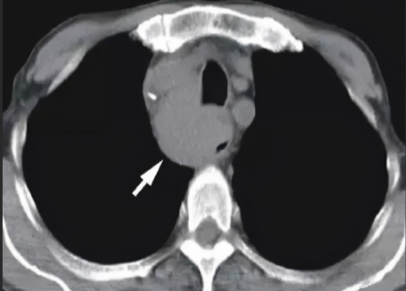

我让患者在门诊做了一个上消化道造影,基本上确诊了。入院后完善检查,明确是食管癌,可惜病变位置太高,如果手术的话需要全食管全喉切除,这对一个41岁的人来说太残忍了,更要命的是发现颈部淋巴结多发转移了,不考虑外科治疗了,这个病人的预后可想而知。